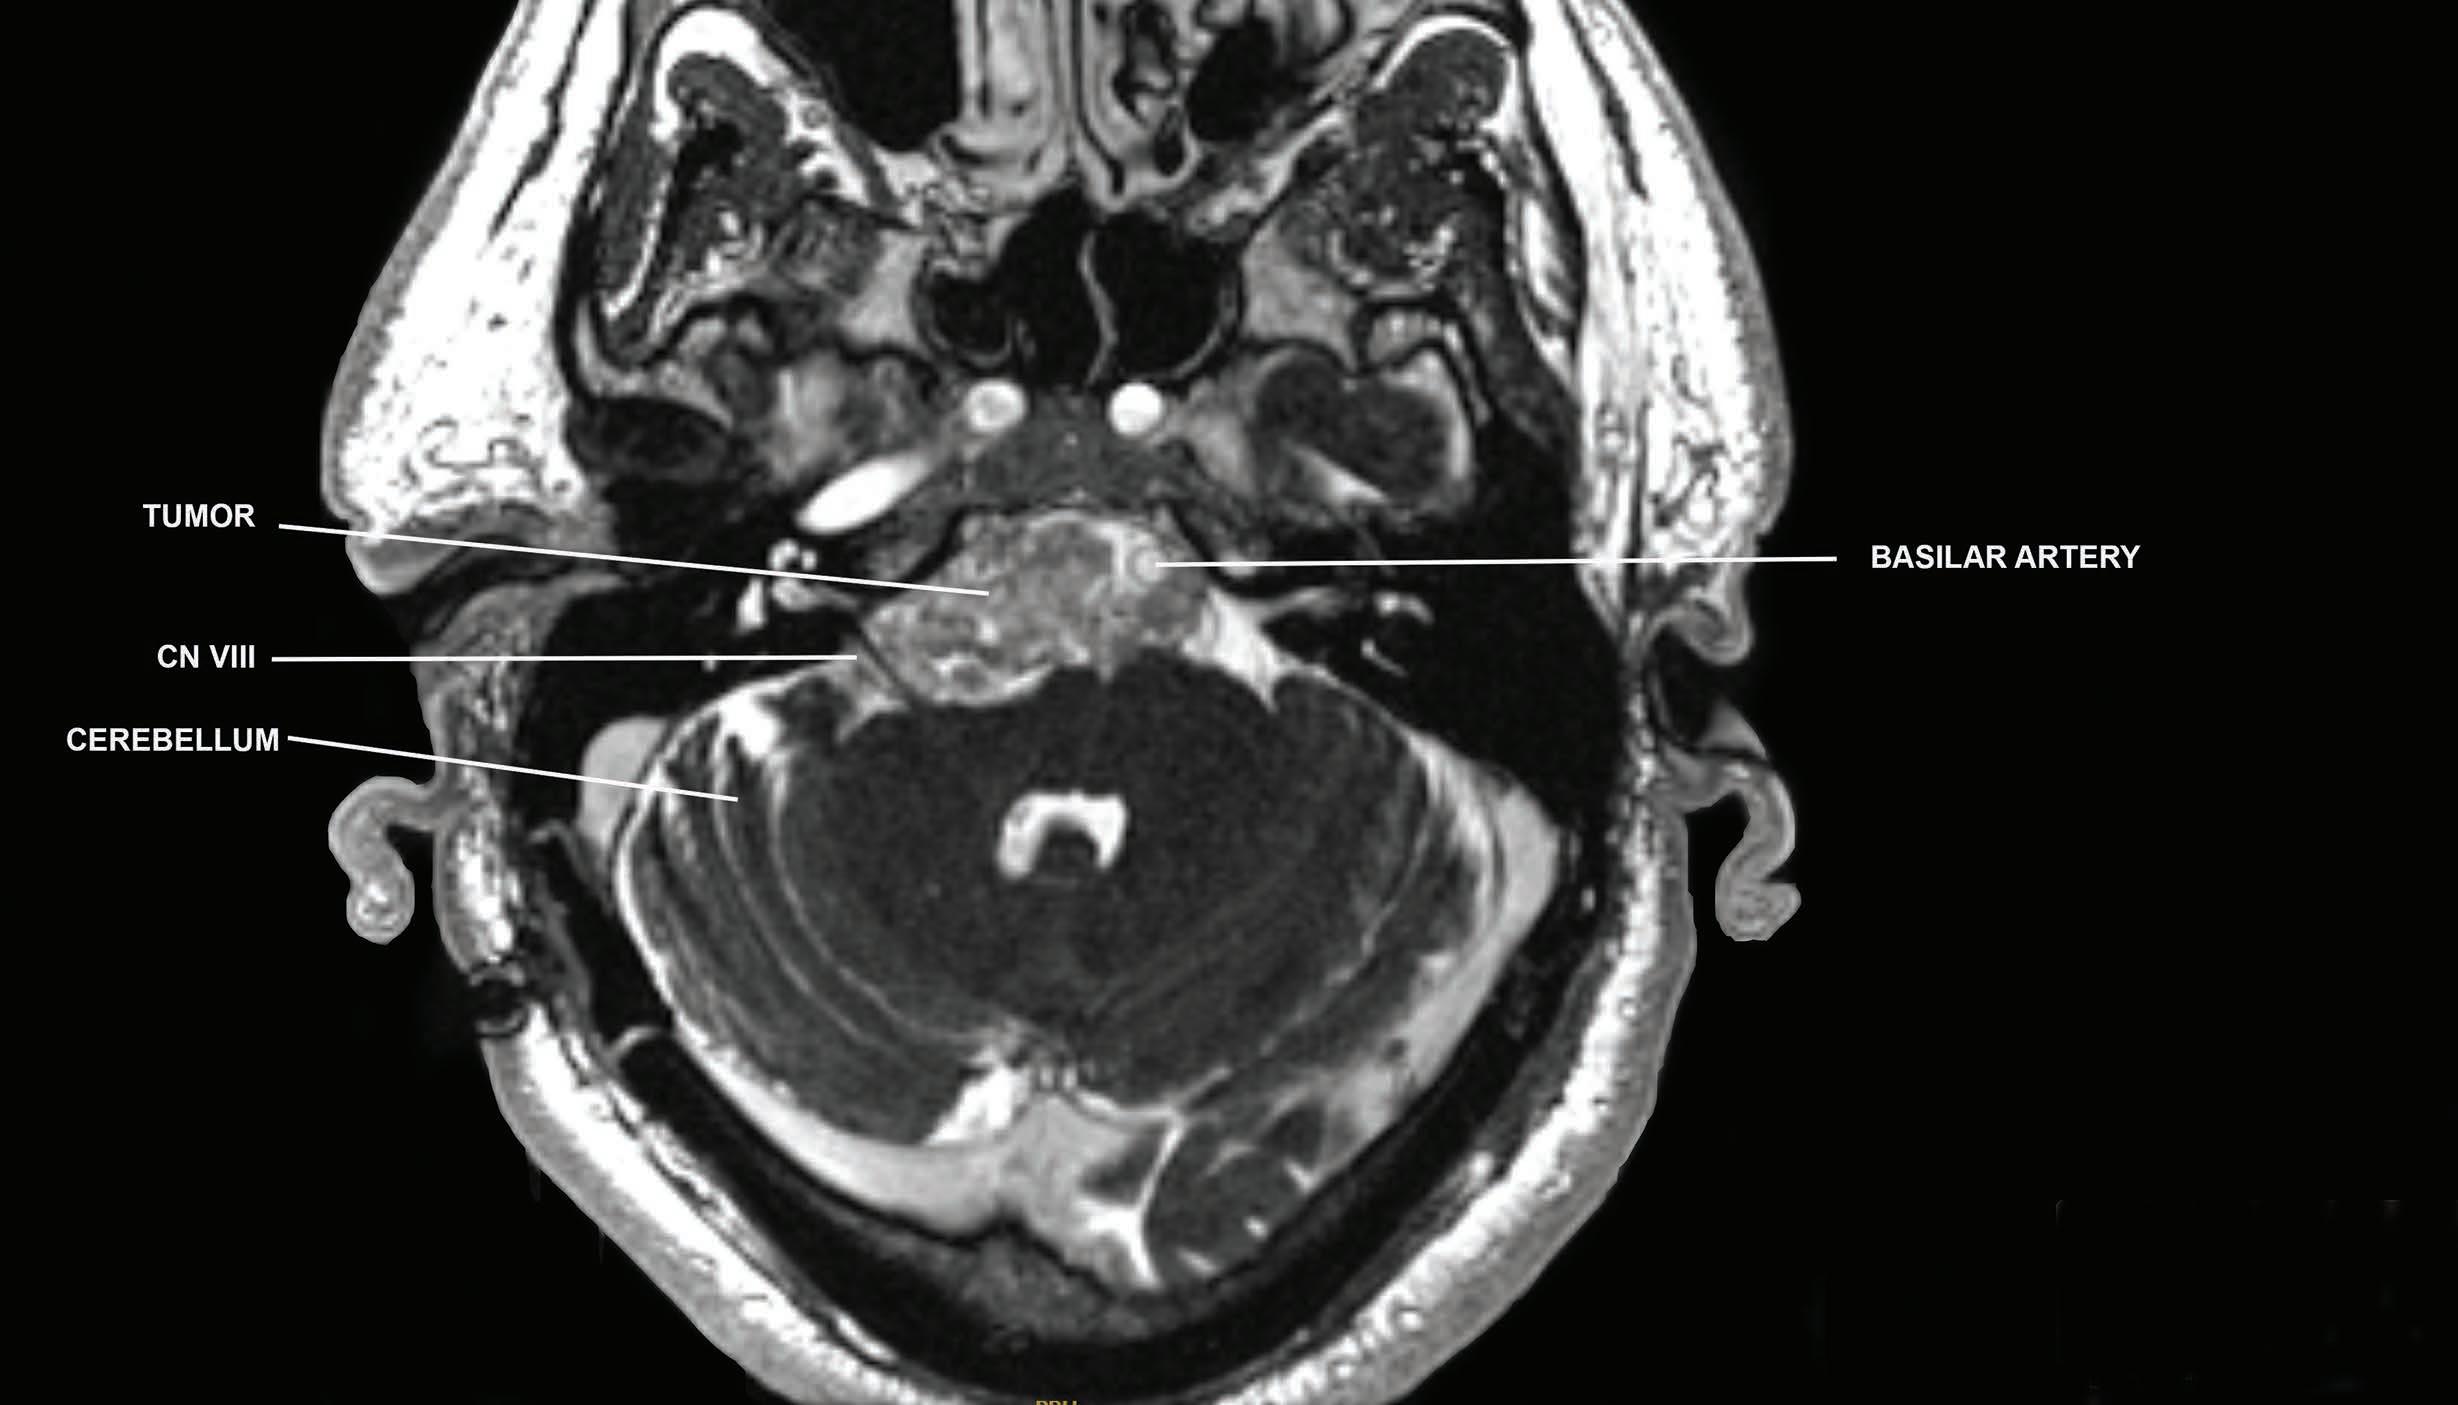

Enormous advances in technology, such as three-dimensional (3D) animation and augmented and virtual reality, are changing how surgeons visualize the brain and then control their instruments during surgery. To help plan a surgical procedure, Dr. Bederson’s colleagues in radiology provide a series of two-dimensional images from a patient’s MRI, CT, and other scans, which are fused together by special software that creates a colorful interactive 3D video of the patient’s brain. Trained members of the team use “Smart Brush” technology to outline preoperative maps and targets that allow Dr. Bederson to optimize his plan. This sophisticated imagery indicates “fly zones” and “no fly zones,” areas within the brain the surgeon can safely approach or should avoid—such as the location of the optic nerve hiding behind a tumor. The images also serve as useful tools for communicating with patients about their operations.

“Patients are facing a complex situation that is often highly stressful,” Dr. Bederson says. “With this technology, we can show patients and their families what we plan to do and explain the rationale for our decisions, such as where we will make an incision and how

we will get to the problem without hurting them. It’s important for patients to know what to expect and how they might be impacted, which also helps build trust and confidence.”

In the operating room, the videos are projected onto a “heads-up display.” A unique microscope injection system overlays the brain “map” directly onto the brain when viewed through Dr. Bederson’s eyepiece as he performs the procedure, much the way a map is projected onto the windshield in the cockpit of a plane. Unlike the GPS navigation system in cars, where the driver must look away from the road to check the GPS device, here the surgeon can view the map and remain entirely focused on the brain without diverting their attention.